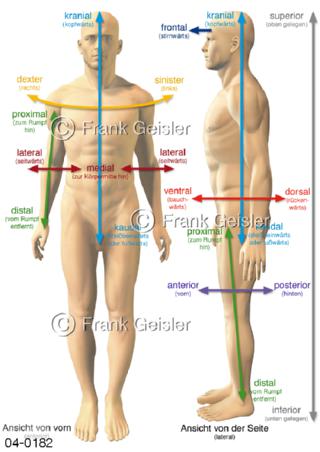

Bildergalerie Topografie Organe

Bilder zur topografischen Anatomie, die Lage der Organe und die Strukturen nach ihren räumlichen Lagebeziehungen zueinander, Übersicht der inneren Organe im Kopf und im Rumpf, Topografie der Organe im Brustraum (Thorax) und im Bauchraum (Abdomen)